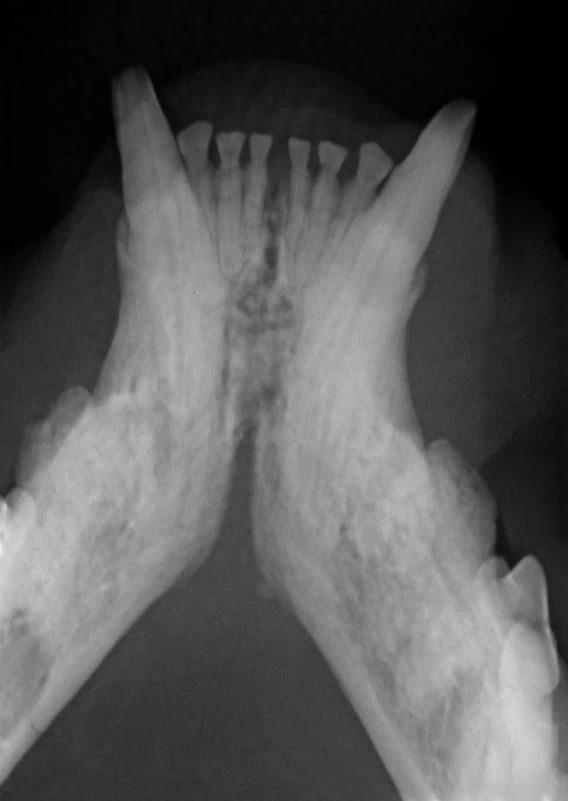

A relaxed and interactive online learning session focused on improving confidence in interpreting dental radiographs in small animal practice.

Each session will review real clinical cases, discussing radiographic findings, common pitfalls, and practical tips for everyday dentistry. We will also include discussion of evidence-based treatment options and clinical decision making.